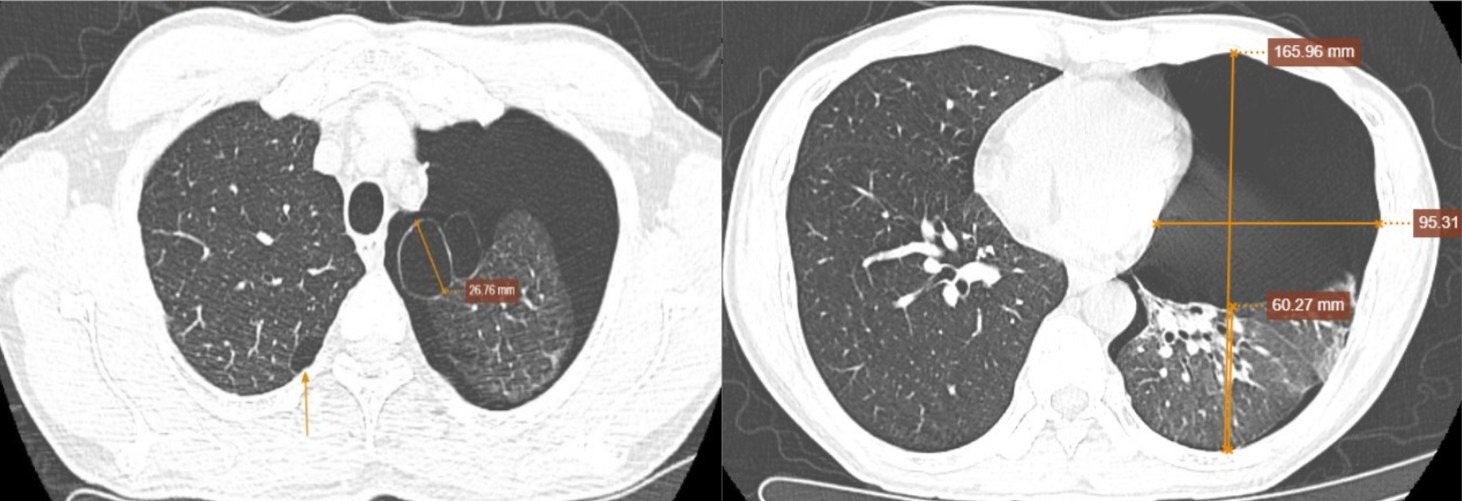

Anh H. được đưa đến khám khi đột ngột xuất hiện đau tức ngực trái như dao đâm, lan lên vai và cánh tay trái, tăng khi thay đổi tư thế hoặc hít thở sâu.

Bên cạnh đó, theo lời bệnh nhân, anh kèm khó thở nhẹ, ho khan, trước đó hoàn toàn khỏe mạnh ngoài tiền sử hút thuốc 30 năm (mỗi hai ngày một bao) và từng phát hiện kén khí phổi vào năm 2022. Gia đình ghi nhận vợ anh từng điều trị lao phổi từ tháng 1 đến tháng 6/2025.

Thăm khám cho thấy bệnh nhân thở nhanh nông, phổi trái thông khí kém, gõ vang, rung thanh giảm, tam chứng Galliard dương tính.

Nhịp tim đều 98 lần/phút, huyết áp 140/90 mmHg, SpO₂ 95%. Kết quả CT liều thấp ghi nhận tràn khí khoang màng phổi trái mức độ nhiều, khiến phổi xẹp thụ động tới 75%, nghĩ nhiều đến nguyên nhân vỡ kén khí.

Hình ảnh còn cho thấy kén khí thùy trên phổi trái và giãn phế nang cạnh vách hai phổi. Siêu âm tim, màng phổi cho thấy tim bị đẩy lệch sang phải, mất dấu trượt màng phổi và không còn đường B-line.

Với chẩn đoán tràn khí màng phổi mức độ nặng do vỡ kén khí, các bác sỹ lập tức tiến hành chọc hút dẫn lưu bằng kim lớn. Chỉ sau 30 phút, tình trạng tức ngực, khó thở của bệnh nhân cải thiện rõ rệt, khí trong khoang màng phổi giảm và anh được chuyển tuyến để can thiệp nội soi xử lý kén khí. Một tuần sau, bệnh nhân hồi phục tốt, không còn đau ngực và đã được xuất viện.